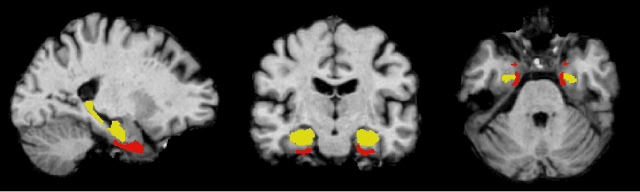

Abstract:Convolutional neural networks have enabled significant improvements in medical image-based disease classification. It has, however, become increasingly clear that these models are susceptible to performance degradation due to spurious correlations and dataset shifts, which may lead to underperformance on underrepresented patient groups, among other problems. In this paper, we compare two classification schemes on the ADNI MRI dataset: a very simple logistic regression model that uses manually selected volumetric features as inputs, and a convolutional neural network trained on 3D MRI data. We assess the robustness of the trained models in the face of varying dataset splits, training set sex composition, and stage of disease. In contrast to earlier work on diagnosing lung diseases based on chest x-ray data, we do not find a strong dependence of model performance for male and female test subjects on the sex composition of the training dataset. Moreover, in our analysis, the low-dimensional model with manually selected features outperforms the 3D CNN, thus emphasizing the need for automatic robust feature extraction methods and the value of manual feature specification (based on prior knowledge) for robustness.